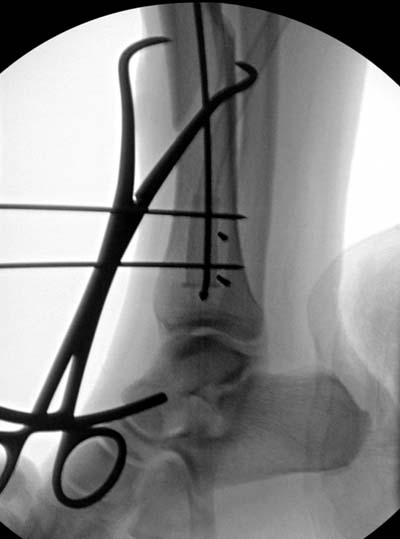

Здесь несколько снимков изолированного перелома большеберцовой с

интактной малоберцовой.  Weber clamp, блокирующие спицы и риминг в

центре канала отрепонировал перелом....